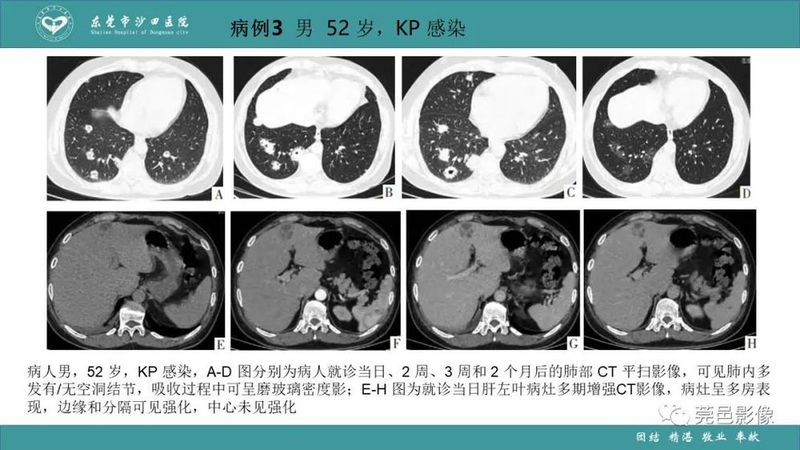

「肺炎克雷伯杆菌肺炎」影像学诊断+鉴别诊断